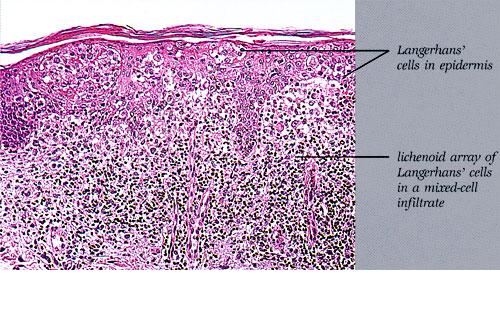

Histiocytosis X =x كثرة المنسجات